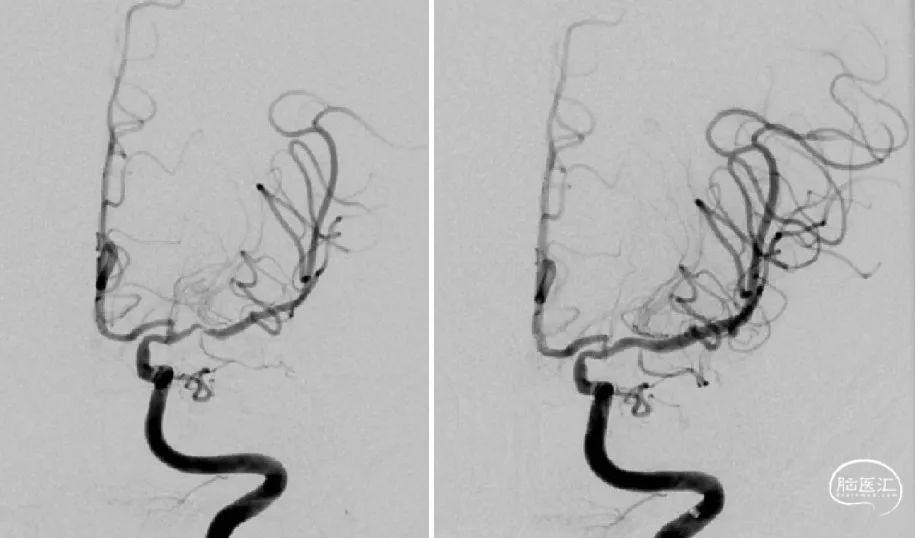

发病一周后完善了脑血管造影检查 。

正位

侧位

左侧大脑中动脉前向血流较同侧大脑前动脉缓慢。

3D:左侧颈内动脉C7段中度狭窄,左侧大脑中动脉M1段重度狭窄。

5、 术后正侧位造影及3D造影

多角度投照显示支架帖壁良好,远端血管显影好,前向血流mTICI3级。